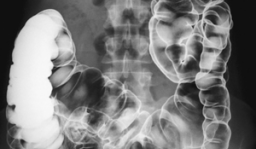

Aparatos de radiodiagnóstico:

• Radiografía de rayos x